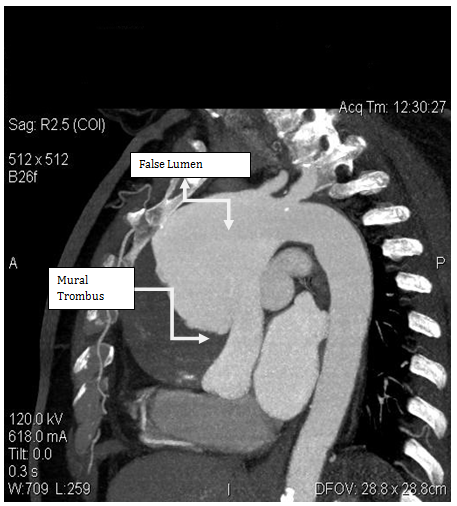

A 62-year-old female patient with known hypertension, obesity history was referred to the cardiology polyclinic by inhalation and diuretic therapy after examination of her chest diseases polyclinic with shortness of breath and rapid fatigue. Blood pressure was measured 130/80 mmHg in both of arm, pulse was 114/m and irregular. Periferal pulses were fuller, faster, arrhtymic on all extremity. Heart sounds were heard as a 3/6 diastolic murmur in aortic focus and 2/6 systolic murmur in mitral focus. Respiratory sounds were normal and equal in both of hemithorax. Hyperlipidemia, impaired fasting glucose, normal renal function were detected in laboratory tests. In echocardiographic examination was revealed ejection fraction %32, mild mitral and tricuspid regurgitation, modarete aortic regurgitation and degeneration at both of valves, aneurismatic dilatation in ascending aorta (9.1 cm) and aortic arch (5.4 cm) were revealed (Figure 1). There was seen dissection fleb in proximal ascending aorta and thrombus was observed in false lumen. Afterwards, that patient was scaned by thoracoabdominal computerized tomography angiography. Diameter of aneursym was measured 9.8 cm and it was extending to the arch aorta (Figure 2 & 3). Dissection and plaque were not seen on carotid doppler ultrasonography. Coronary angiography was not applied to patient before surgery operation because of high risk. Supracoronary Graft Interposition and Hemiarchus Replacement was applied to patient after preparations were completed (Figure 4 & 5). Prostetic aortic valve replacment was not performed to patient because of there was no pathology other than degeneration. Control echocardiography was performed after intensive care process. Ejection fraction was measured %55 and seen mild mitral-aortic-tricuspid regurgitation. The patient was discharged after 6 days without any problems in the postoperative period.

Figure 3: Computerized Tomography Angiography Image of Ascending Aort Aneursym with chronic dissection.

Even though abdominal aortic aneursym is seen the most frequently, thoracic aortic aneursym have different importance because of it is quite as development of rupture and dissection clinic. Early diagnosis and treatment prevent from mortality. In the recently published European Cardiology Society Guide to Aortic Diseases (2014) surgical borders are as follows; 45 mm in patients with Marfan's syndrome, 50 mm in patients with bicuspid aortic valve and 55 mm in the other patient group [4]. In our patient, the diameter of ascending aorta was measured as 98 mm in the widest place. Thoracic CT angiography provides us with the most accurate results in terms of assessing how far and where the aneurysm has been measured and how far it has been measured, even though echocardiography is required routine evaluation in outpatient. We also want to emphasize the importance of multimodality imaging in this case.